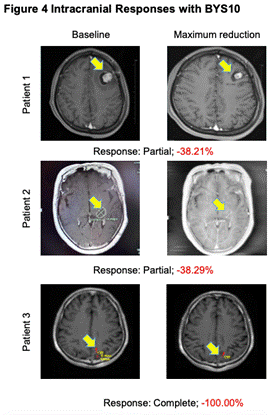

高效入脑���:BYS10治疗伴脑转移RET突变实体瘤实现颅内缓解

研究人员在4例至少有1个可测量颅内病灶(1例颅内完全缓解)的患者中观察到颅内抗肿瘤活性��。

图4.颅内抗肿瘤活性

从本次ASCO大会所公布的高选择性RET抑制剂BYS10公布了首项Ⅰ/Ⅱ期人体研究结果来看,BYS10在RET实体瘤治疗领域具有非常大的潜力:首先,安全性结果充分表明,BYS10治疗RET突变实体瘤的安全性良好,3-4级TRAE及严重不良反应的发生率低,利于患者长期管理��。其次,初步疗效数据结果显示,患者治疗后的ORR为62.5%,DCR为85%,这表明近三分之二的患者经过BYS10治疗能够有效实现疾病缓解,超过五分之四的患者能够实现疾病控制,尤其TC和MTC患者的DCR可达到100%。在临床上更为常见的NSCLC患者中,BYS10治疗的ORR能够达到60%,DCR能够达到80%,充分展现了BYS10的治疗潜能���。此外,对于临床上十分关注的脑转移患者,经BYS10治疗后可实现颅内病灶的有效缓解,证实了BYS10的颅内病灶控制潜能����。